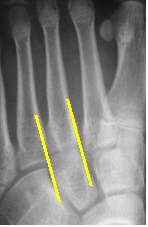

The normal midfoot